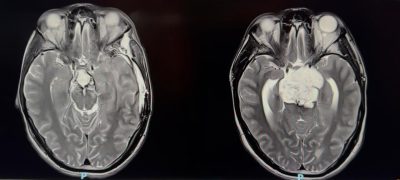

نجح فريق طبي سعودي في مستشفى الملك فهد بجدة عضو تجمع جدة الصحي الثاني بقيادة د. هاني القرشي في استئصال ورم حبلي نادر ومعقد من قاع الجمجمة، خلال ثلاث عمليات جراحية متتالية استغرقت ٣٥ ساعة. الورم كان ضاغطًا على جذع الدماغ والأعصاب القحفية، وتعامل معه الفريق بتقنيات جراحية متقدمة لا تُجرى إلا في مراكز عالمية محدودة، ولله الحمد المريض تعافى وعاد لحياته الطبيعية دون أي عجز عصبي يذكر.